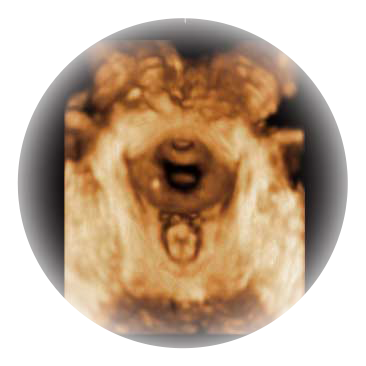

大角度腔内容积探头,可完整包络子宫及盆底结构,充分展示组织结构毗邻关系。